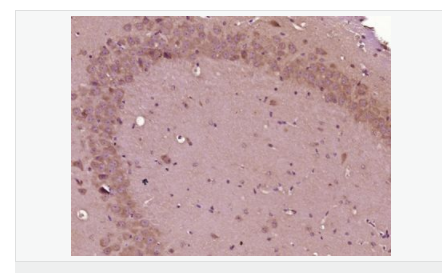

產(chǎn)品介紹This gene encodes the epsilon member of the sarcoglycan family. Sarcoglycans are transmembrane proteins that are components of the dystrophin-glycoprotein complex, which link the actin cytoskeleton to the extracellular matrix. Unlike other family members which are predominantly expressed in striated muscle, the epsilon sarcoglycan is more broadly expressed. Mutations in this gene are associated with myoclonus-dystonia syndrome. This gene is imprinted, with preferential expression from the paternal allele. Alternatively spliced transcript variants encoding different isoforms have been found for this gene.[provided by RefSeq, Oct 2010]

Component of the sarcoglycan complex, a subcomplex of the dystrophin-glycoprotein complex which forms a link between the F-actin cytoskeleton and the extracellular matrix.

Tissue Specificity:

Ubiquitous.

DISEASE:

Defects in SGCE are a cause of dystonia type 11 (DYT11) [MIM:159900]; also known as myoclonic dystonia or alcohol-responsive dystonia. DYT11 is a myoclonic dystonia. Dystonia is defined by the presence of sustained involuntary muscle contractions, often leading to abnormal postures. DYT11 is characterized by involuntary lightning jerks and dystonic movements and postures alleviated by alcohol. Inheritance is autosomal dominant. The age of onset, pattern of body involvement, presence of myoclonus and response to alcohol are all variable.